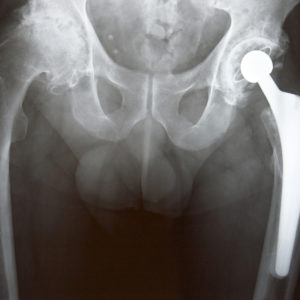

Hip implant liners, also known as acetabular liners, are one of several parts of a complete hip implant. Made of plastic or ceramic, they often line the area between the ball of the hip socket and the cup it fits into to allow the implanted components to move freely and smoothly.

The Connexion GXL acetabular liner, manufactured by Exactech and made from a plastic called polyethylene, was designed to be used in total hip replacement surgeries (primary and revision) working with other Exactech brand hip replacement systems (Acumatch, MCS Systems and Novation). The liners are typically used for those who need a total hip replacement due to joint-degrading conditions such as osteoarthritis and rheumatoid arthritis, and bone damage resulting from trauma or disease.

Exactech’s communication to surgeons recommended that GXL patients who are less than six years from index surgery and who have not been seen in over 12 months, return to their physician for a routine clinical exam and x-rays to properly evaluate the status of their implant.